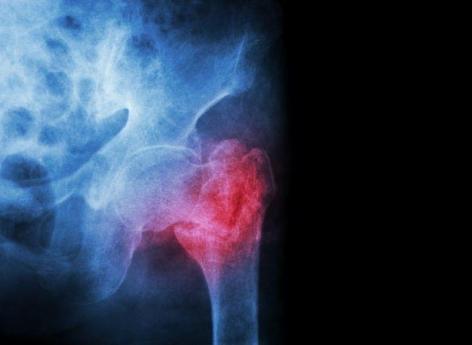

Réduction de la taille, douleurs intenses dans le dos…maladie dite "silencieuse", l’ostéoporose n’en est pas moins un vrai problème pour beaucoup de personnes passé l’âge de 65 ans. Affliction osseuse liée au vieillissement, elle se caractérise par une diminution de la densité de l’os et des modifications de sa microarchitecture. L’os est plus fragile et le risque de fracture augmente. Parmi les facteurs intervenant dans la régulation de la masse osseuse, la vitamine D mais surtout les hormones sexuelles. La maladie est notamment connectée aux changements hormonaux liés à la ménopause et bien qu’elle puisse également toucher les hommes, est surtout répandue chez les femmes ménopausées. Pour donner une idée en termes de chiffres, en Europe et aux Etats-Unis, 30% des femmes ménopausées présenteraient de l’ostéoporose.

Chez certains, la perte de masse osseuse n’aura pas de conséquences graves, mais chez d’autres, l’accélération anormale de la résorption osseuse non compensée par une formation osseuse suffisante entraînera une perte excessive de la masse osseuse et de sa résistance. On parle alors d’ostéoporose. Quand la maladie débute, le médecin traite d’abord une éventuelle carence en vitamine D et ou en calcium, notamment en encourageant son patient à changer son alimentation. Il l’incite également à faire plus d’activité physique, à réduire sa consommation d’alcool et de sel et à arrêter le tabac s’il est fumeur. Mais si la maladie se confirme et empire, il pourra prescrire différents médicaments. Parmi eux, les biphosphonates. Certains ayant associé ces derniers à une chute des dents, Pourquoi Docteur fait aujourd’hui le point.